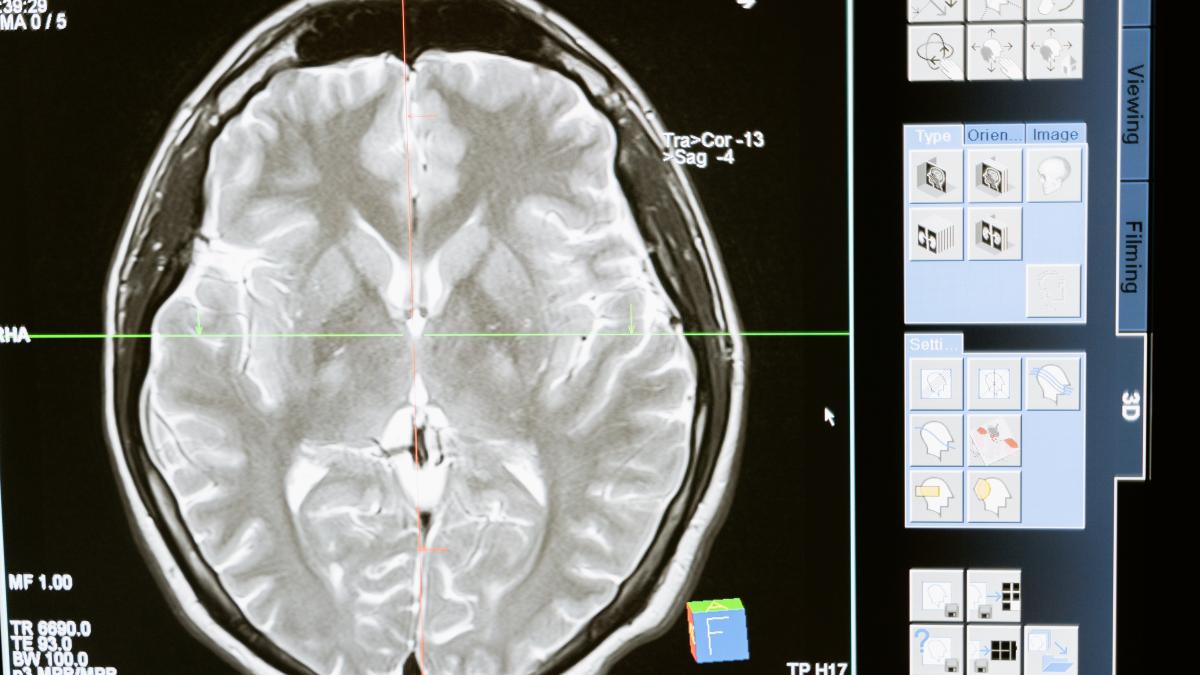

Un rezident din Florida a murit după ce s-a infectat cu o amibă rară care mănâncă creierul, spun oficialii.

Naegleria fowleri infectează creierul prin nas. Infecțiile sunt aproape întotdeauna fatale, potrivit Centrelor pentru Controlul și Prevenirea Bolilor din SUA (CDC).

Persoanele care sunt infectate contractă o boală numită meningoencefalită amibiană primară.

Simptomele includ dureri de cap, febră, greață, vărsături, dezorientare, gât înțepenit, pierderea echilibrului, convulsii și/sau halucinații.